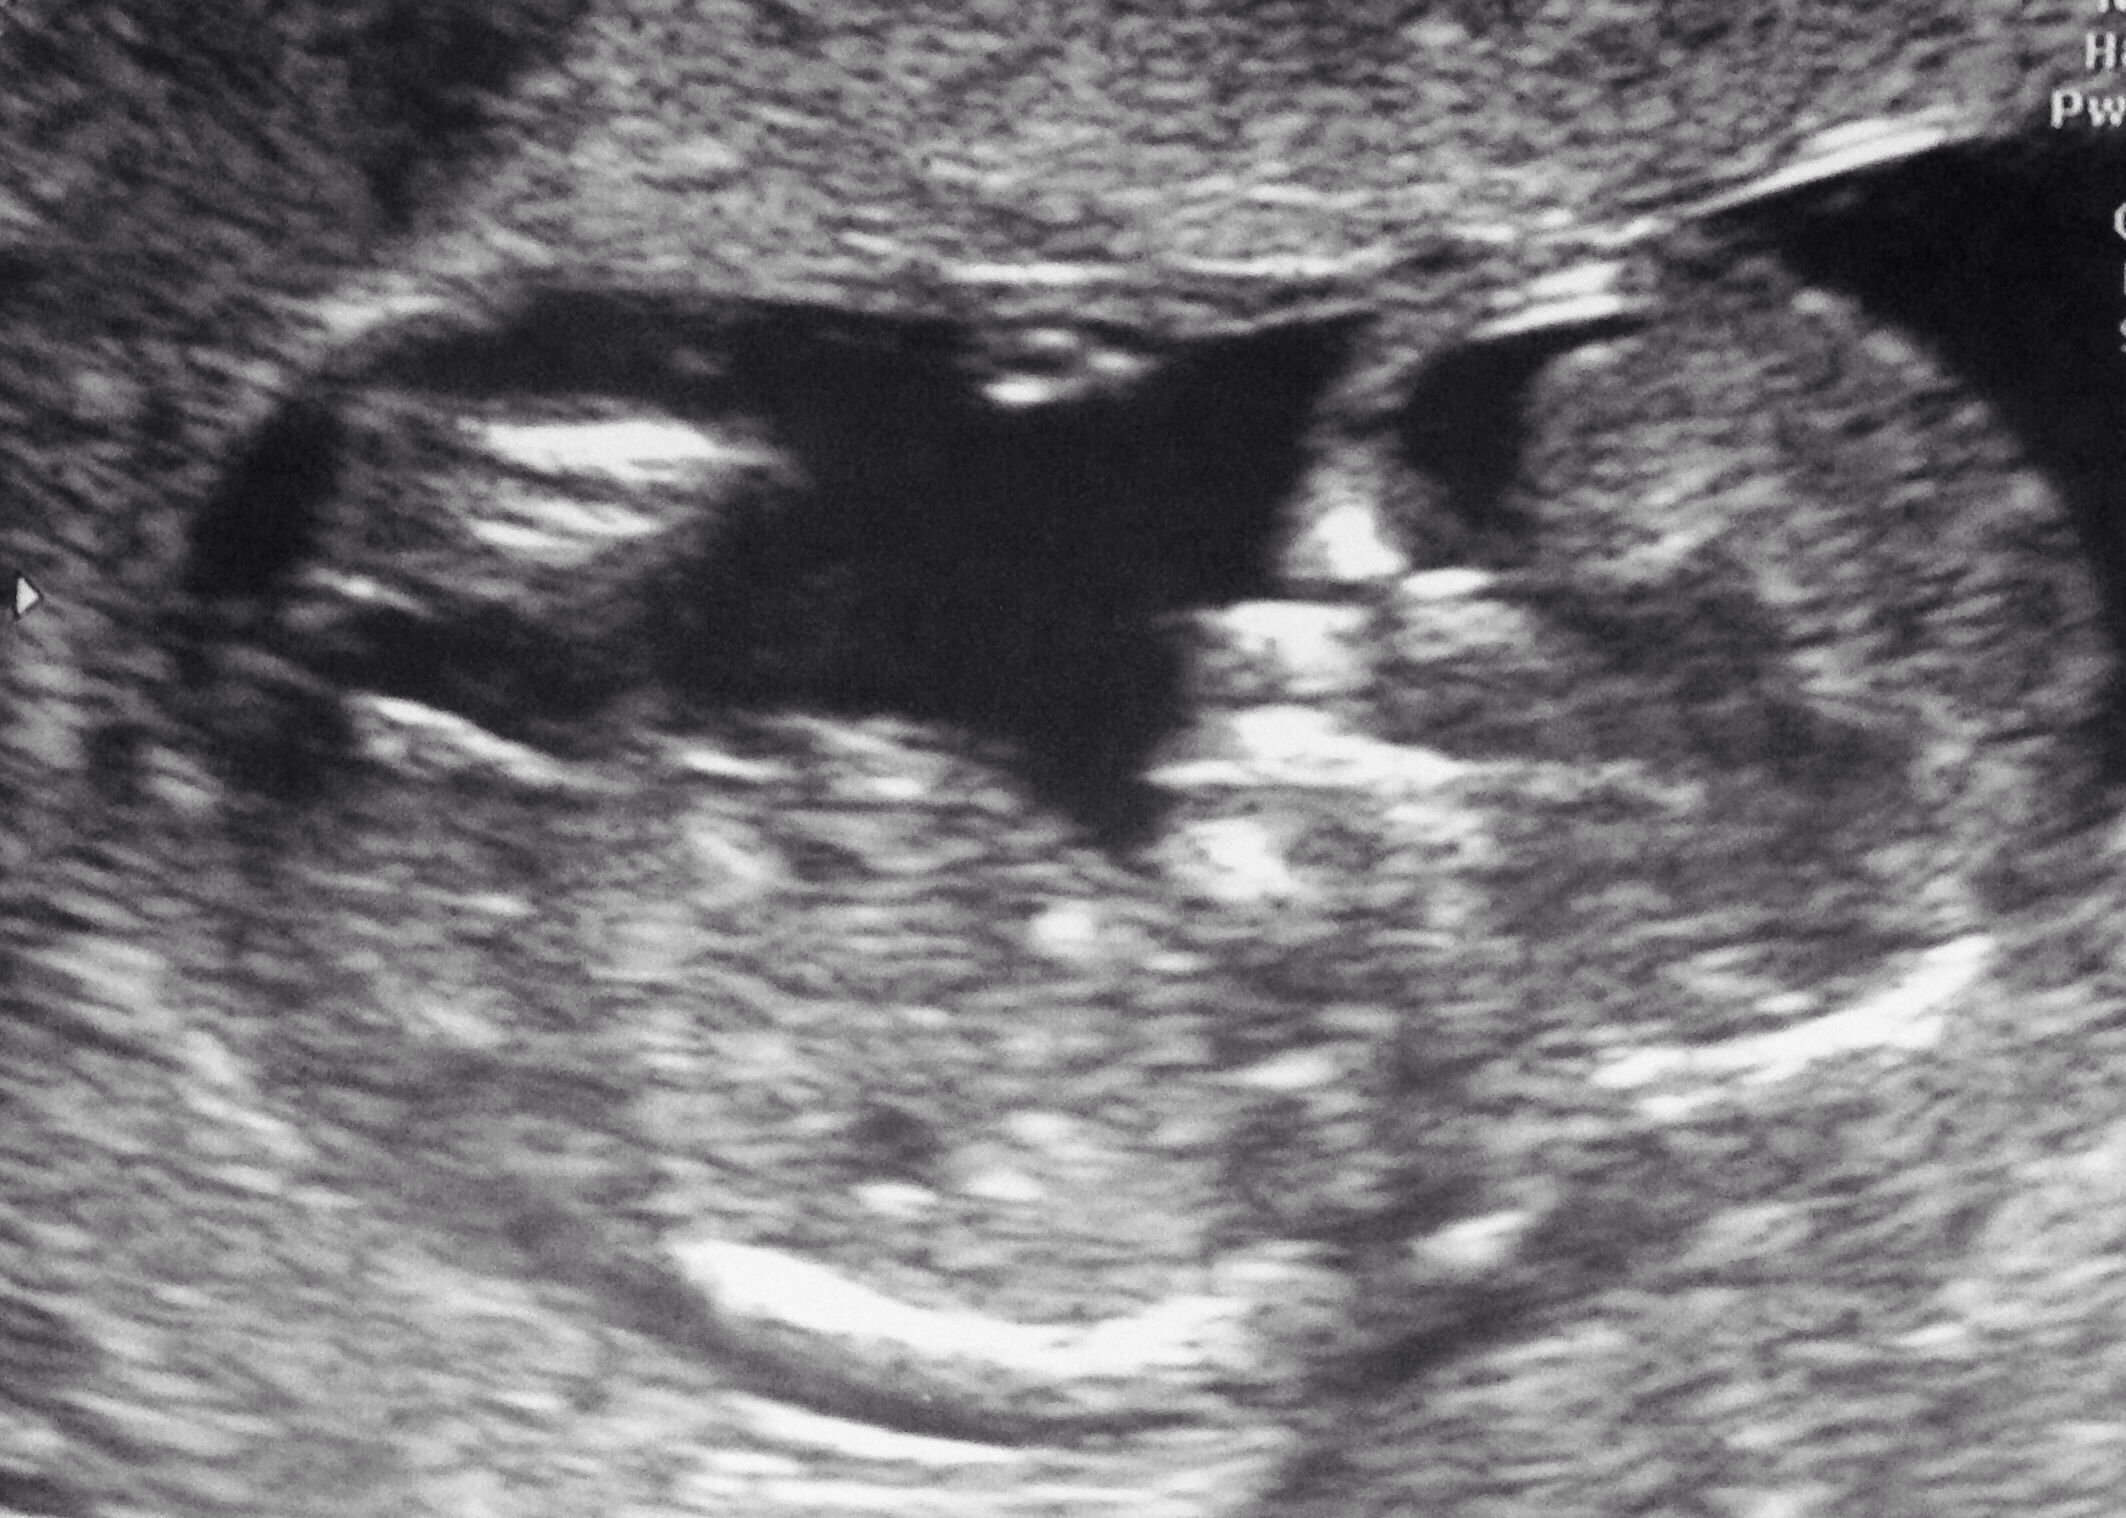

I'm 12+3 had my USS yesterday :)

Very girly! But early but don't see it rising either;)

Leaning girl good luck